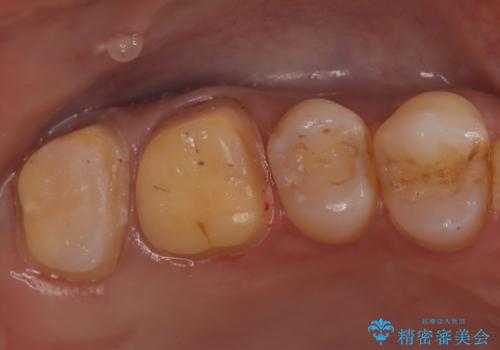

- 左上の奥歯がズキズキ痛い、冷たいものも長引く痛みがあると来院されました。

根管治療を行った後にオールセラミッククラウンにて修復しております。